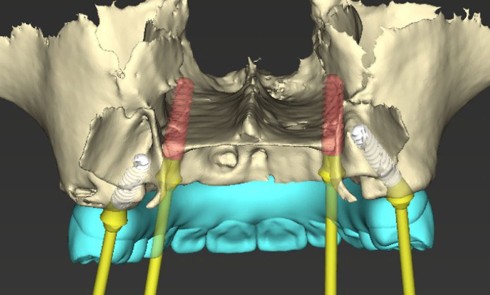

Article réservé à nos abonnés Implantologie 2.0 : gestion digitale dans le traitement de l’édenté complet

Contexte clinique et objectifs Une patiente partiellement édentée mandibulaire se présente avec les dents 33, 35, 36 et 43 compromises (alvéolyse...